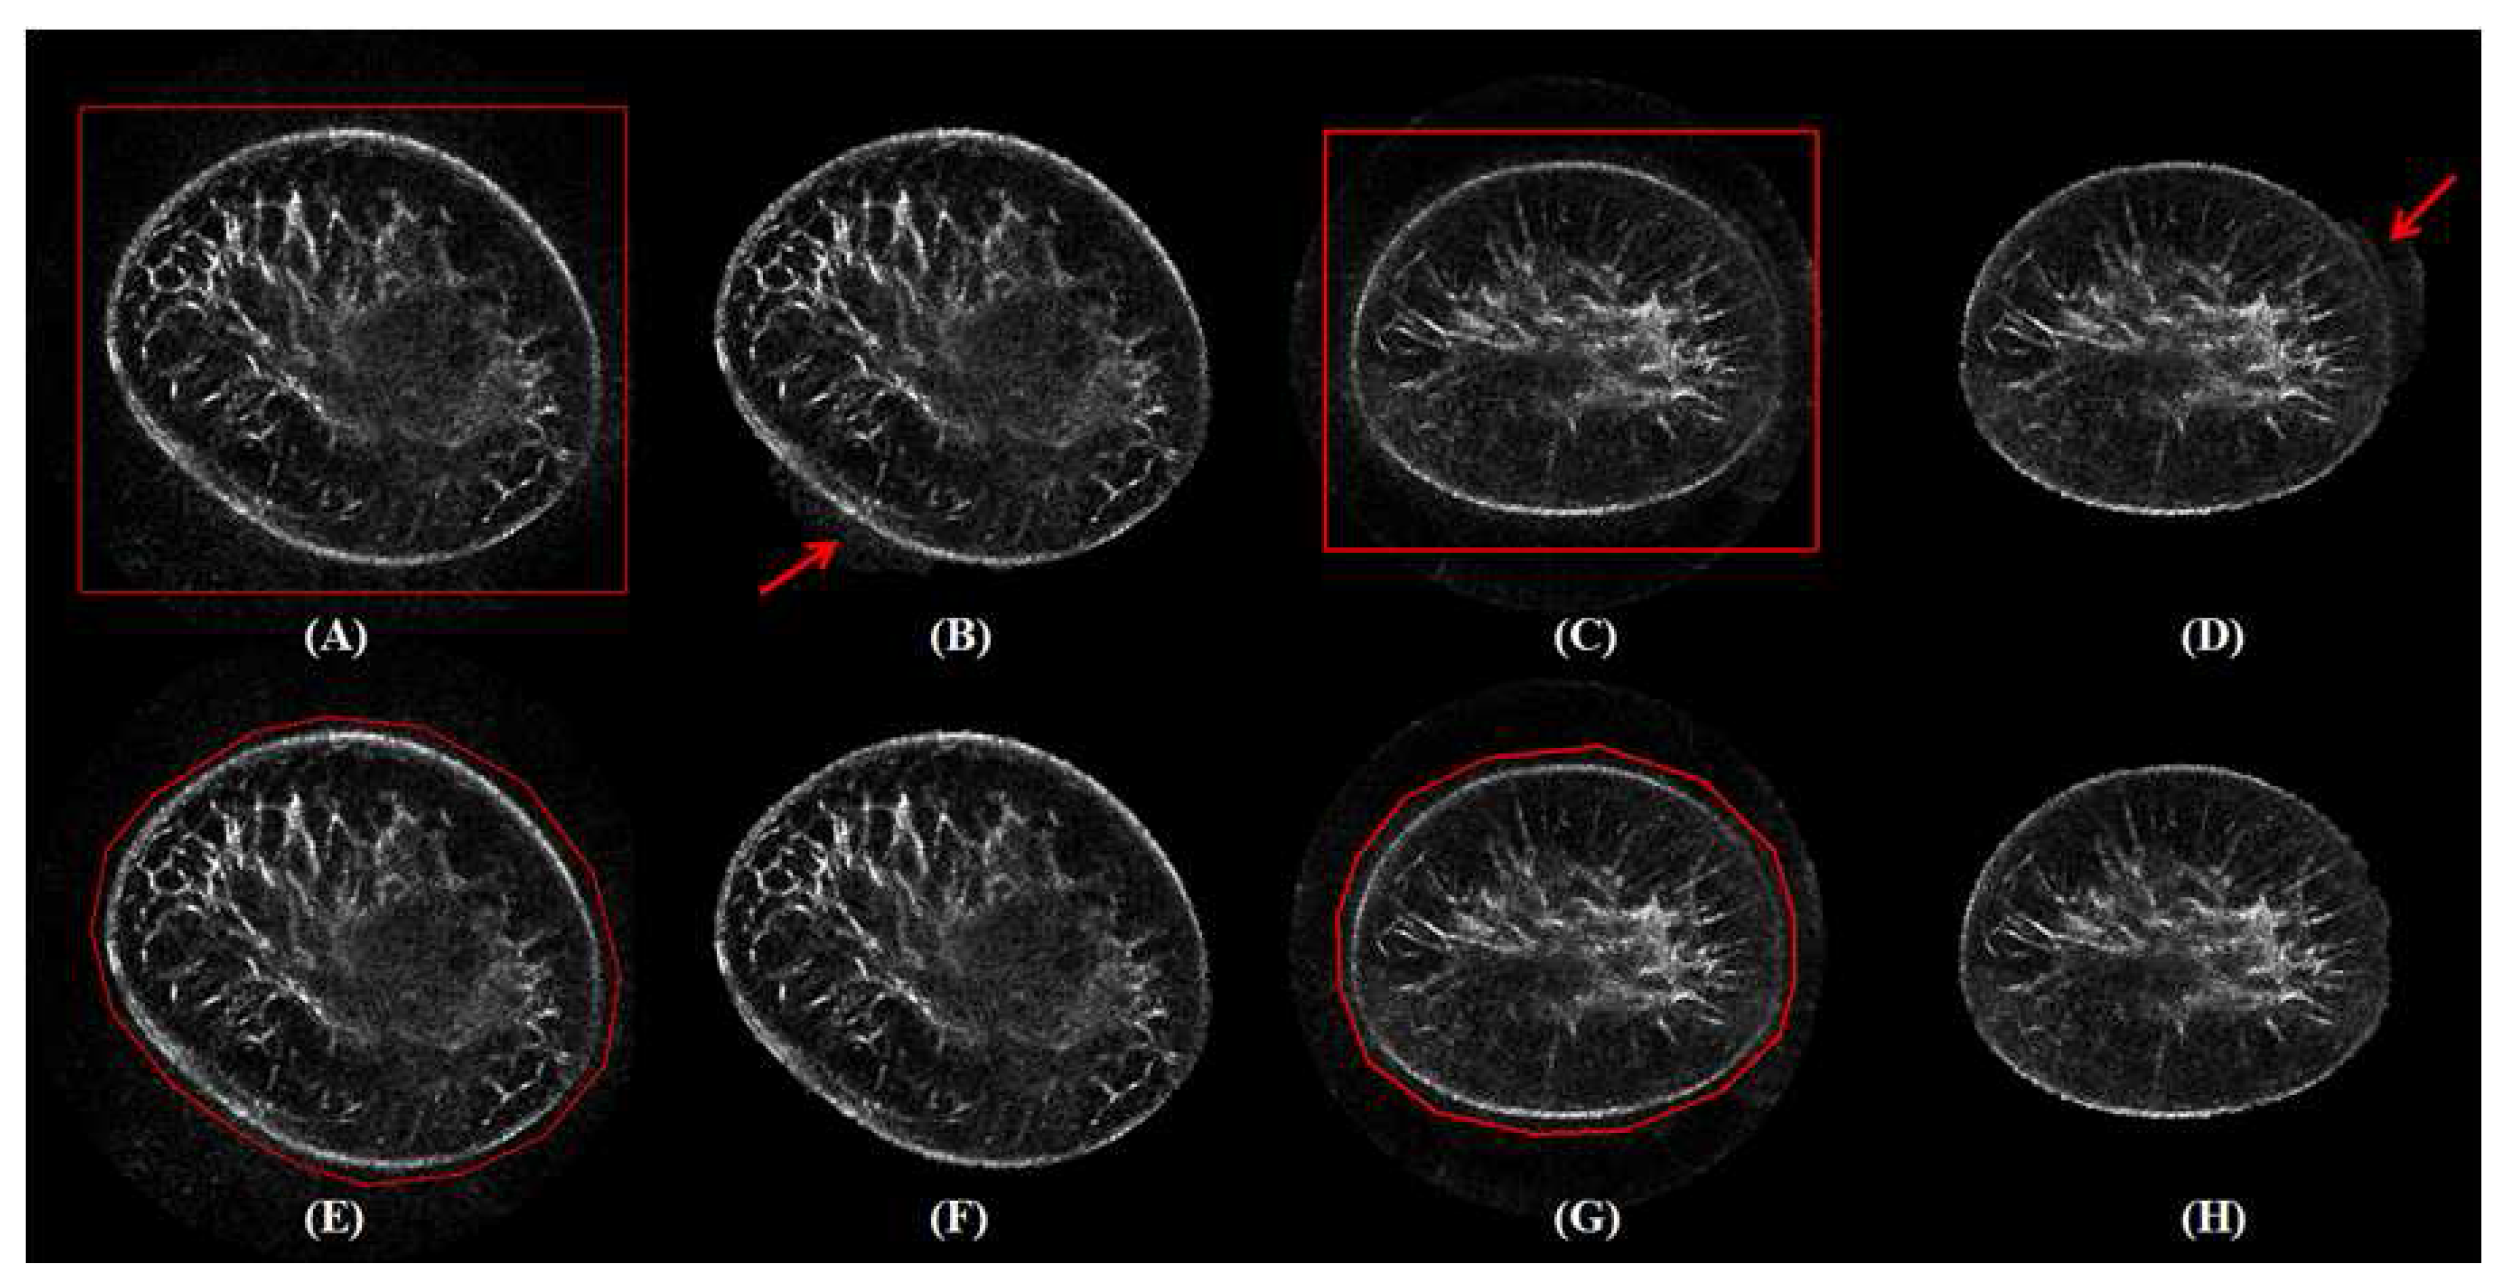

3.5. Robustness

3.6. Failure Case Analysis